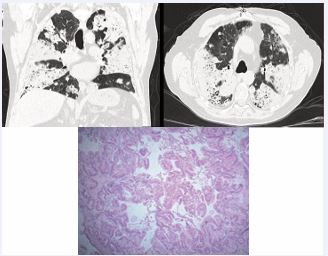

78 year-old man referred to pulmonology for dyspnea, dry cough, and abnormal CT Chest showing consolidative changes in all lobes. Patient had failed multiple antibiotic courses for presumed bacterial pneumonia as well as a steroid course for organizing pneumonia. Infectious and autoimmune work up negative. Given sarcoidosis, organizing pneumonia, eosinophilic pneumonia would respond to steroids, underwent bronchoscopy with biopsy due to concern for Pulmonary Alveolar Proteinosis or malignancy. Bronchoscopy with transbronchial biopsy showed atypical mucinous cell proliferation. Lung biopsy via Video Assisted Thoracoscopic Surgery showed mucinous adenocarcinoma (MA) which is an uncommon subtype of lung adenocarcinoma. It responsible for 2.2 3.9% of resected adenocarcinomas [1]. The most frequent symptoms are dyspnea, cough with sputum and fever which are nonspecific and mimic pneumonia. Typical chest CT findings of organizing pneumonia include peripheral, bilateral, wedge-shaped ground glass or consolidative changes (photonegative pulmonary edema) which are very similar to the radiologic presentation of MA which include multicentric opacities or consolidation, ground glass opacities, and nodules, commonly located in the lower lobes [2,3]. Given its slow growing nature, PET-CT avidity would be low, therefore not helpful. According to Liu et al. the yield of surgical lung biopsy and CT-guided percutaneous lung biopsy had a diagnostic yield of 100%, TBLB combined with bronchoalveolar lavage had a diagnostic yield of 80.9% [4] (Figure 1).

Figure 1 H&E slides show lung parenchyma that has been replaced with confluent neoplastic columnar cells with mucinous cytoplasm. Supportive immunostains (not pictured) showed the neoplastic cells are positive for CK7 while being negative for CK20 and CDX2, compatible with a well differentiated mucinous lung adenocarcinoma.